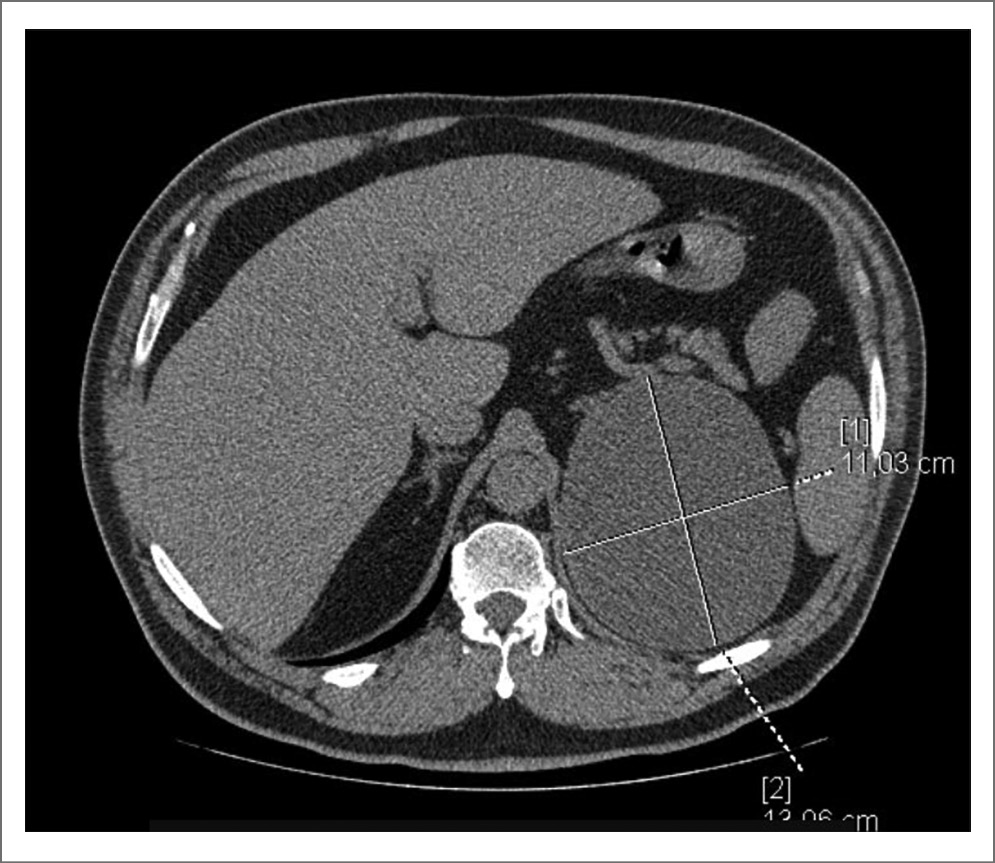

Стоит отметить клинический случай пациента из нашего исследования с кистой почки категории IIF диаметром до 131 мм в верхнем сегменте с тонкой капсулой и наличием пристеночного мягкотканного компонента, не накапливающего контраст. На рис. 1–4 представлены снимки мультиспиральной КТ пациента до операции с внутривенным контрастированием в различных срезах с демонстрационными измерениями. Выполнено оперативное вмешательство – лапароскопическое иссечение стенки кисты. В ходе операции после вскрытия стенки образования эвакуировано до 650 мл коричневой жидкости с желто-коричневыми хлопьями. При получении гистологического заключения верифицирован почечно-клеточный рак, проведена радикальная нефрэктомия в отсроченном порядке. Морфологическое исследование удаленной почки после повторного оперативного вмешательства подтвердило диагноз папиллярной карциномы, тип 2, G2 по Fuhrman. Т3N0M-R0.

Рис. 1. Киста левой почки. Аксиальный срез. Нанесены измерения в максимальном размере образования.